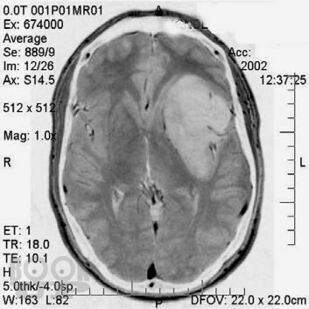

Кратко изложены этиология, особенности эпидемиологии, патогенеза, классификация и основные клинические проявления первичных опухолей головного мозга, современные принципы клиники, диагностики и оказания госпитальной помощи больным с данной патологией. Представлены алгоритмы обследования и лечения больных с наиболее часто встречающимися опухолями в зависимости от стадии течения патологического процесса.